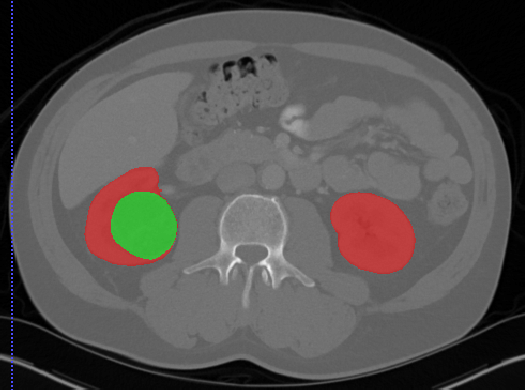

kits19.png